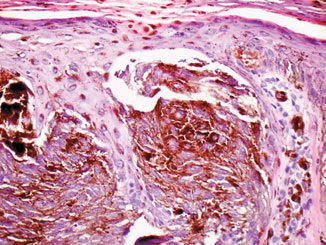

Pernio = الشرث Pernio (Chilblain) Pernio (chilblain) is a distinct form of cold-induced injury in which humidity, in addition to cold, plays a role in inducing the condition . There are acute and chronic presentations. Chilblains classically presents in young to middle-aged women as painful, burning, and/or pruritic erythematous to violaceous or cyanotic macules, papules, […]